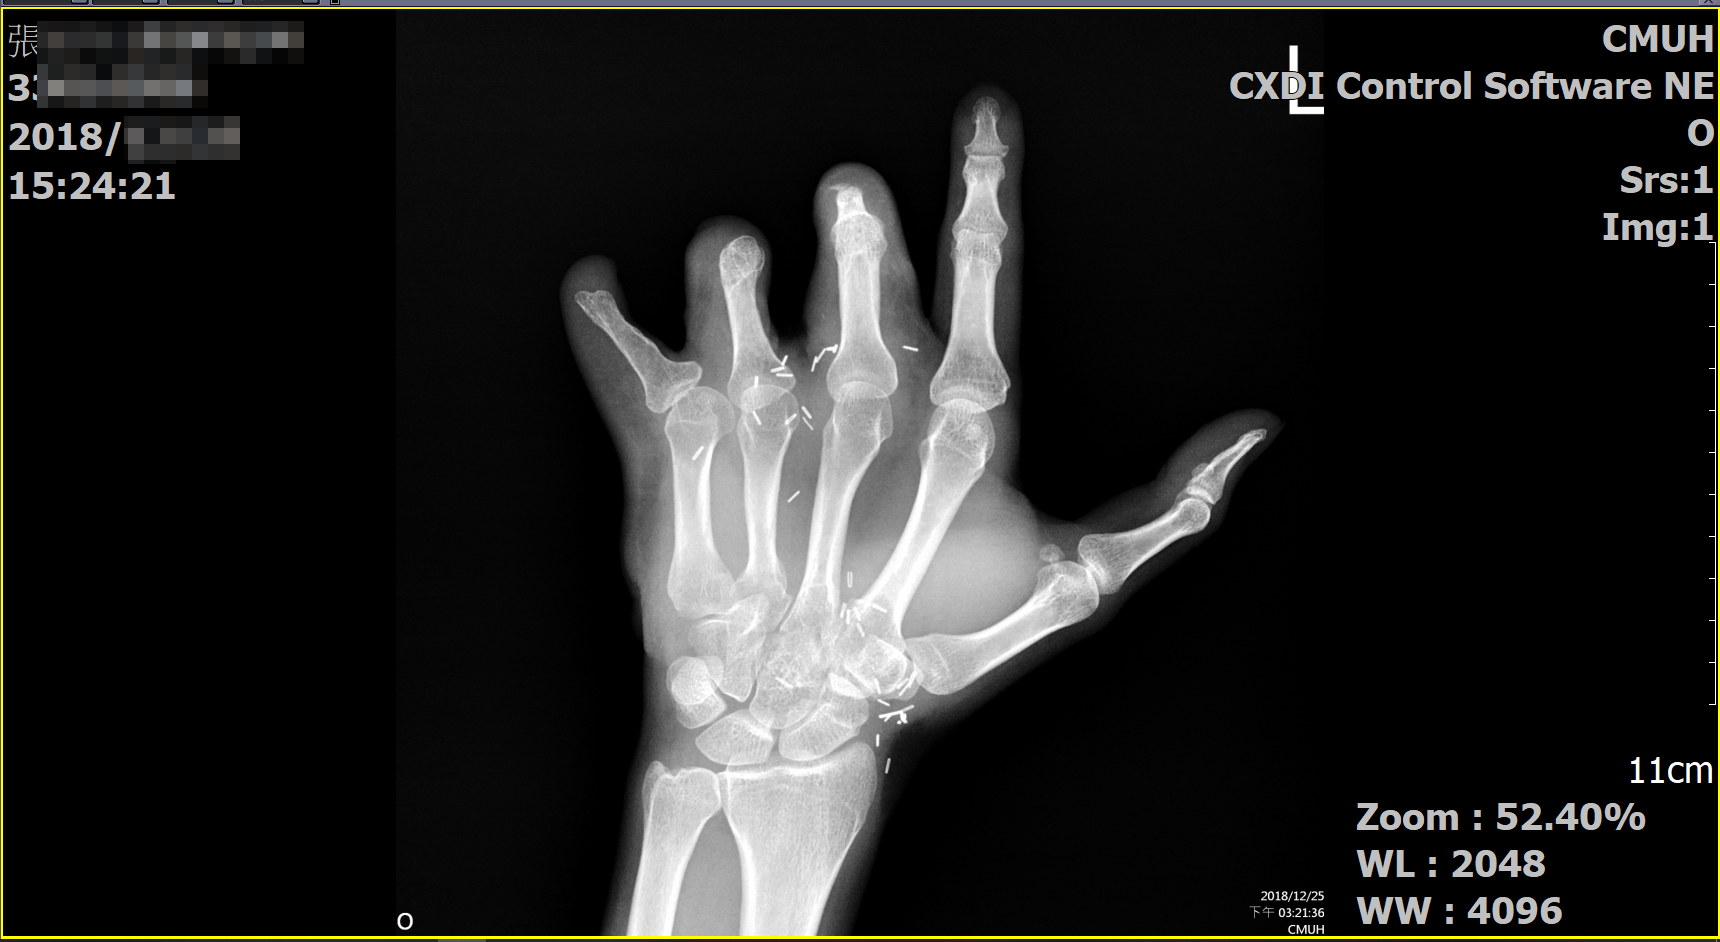

張先生於公司加工區進行加工作業,為了將加工件從機台取出,導致左手第三、四、五指節遭機台捲入碾壓,經醫師施行截斷手術,於恢復期過後自行向勞保局申請失能給付,經勞保局審查後給付第11等級職業傷病失能給付,張先生在復健時遇到佑安業務,經評估後發覺勞保局核付第11等級應有錯誤,故張先生決定交給佑安來處理。

截指X光片︰